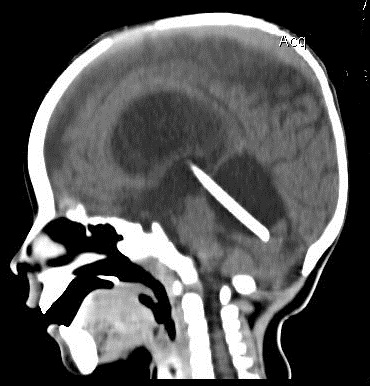

МРТ снимки мальформации Денди-Уокера